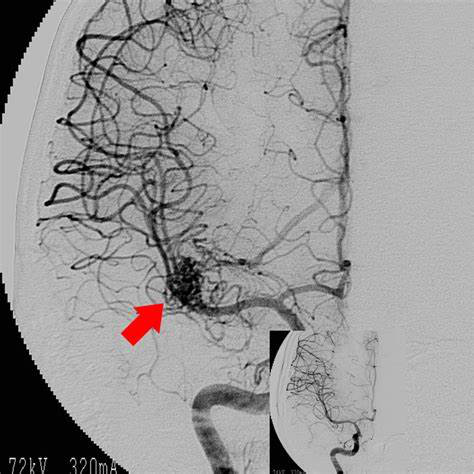

答:腦動(dòng)靜脈畸形是先天性的,是畸形的動(dòng)脈和靜脈簇彼此直接相連。由于它是先天性畸形,醫(yī)生不知道它會(huì)多久破裂。

首先,如果出現(xiàn)腦動(dòng)靜脈畸形,很容易破裂,但動(dòng)脈和靜脈的壁厚不同。動(dòng)脈負(fù)責(zé)將心臟發(fā)出的血液輸送到每個(gè)地方,但是血液流動(dòng)劇烈,足以打動(dòng)血管,但是靜脈只是壁厚,因?yàn)樗粫?huì)將用過(guò)的血液返回心臟是不同的。

正常人通過(guò)毛細(xì)血管穿過(guò)動(dòng)脈并放松血液流動(dòng)并流入靜脈。腦動(dòng)靜脈畸形不穿過(guò)毛細(xì)血管,而直接流入壁上的細(xì)靜脈,從而導(dǎo)致破裂和腦出血

腦出血的原因多種多樣,但由于壁厚的動(dòng)脈血管和壁薄的細(xì)靜脈通過(guò)多余的血管連接,因此腦動(dòng)靜脈畸形的原因被損害。

破裂的可能性取決于腦動(dòng)靜脈畸形的大小。